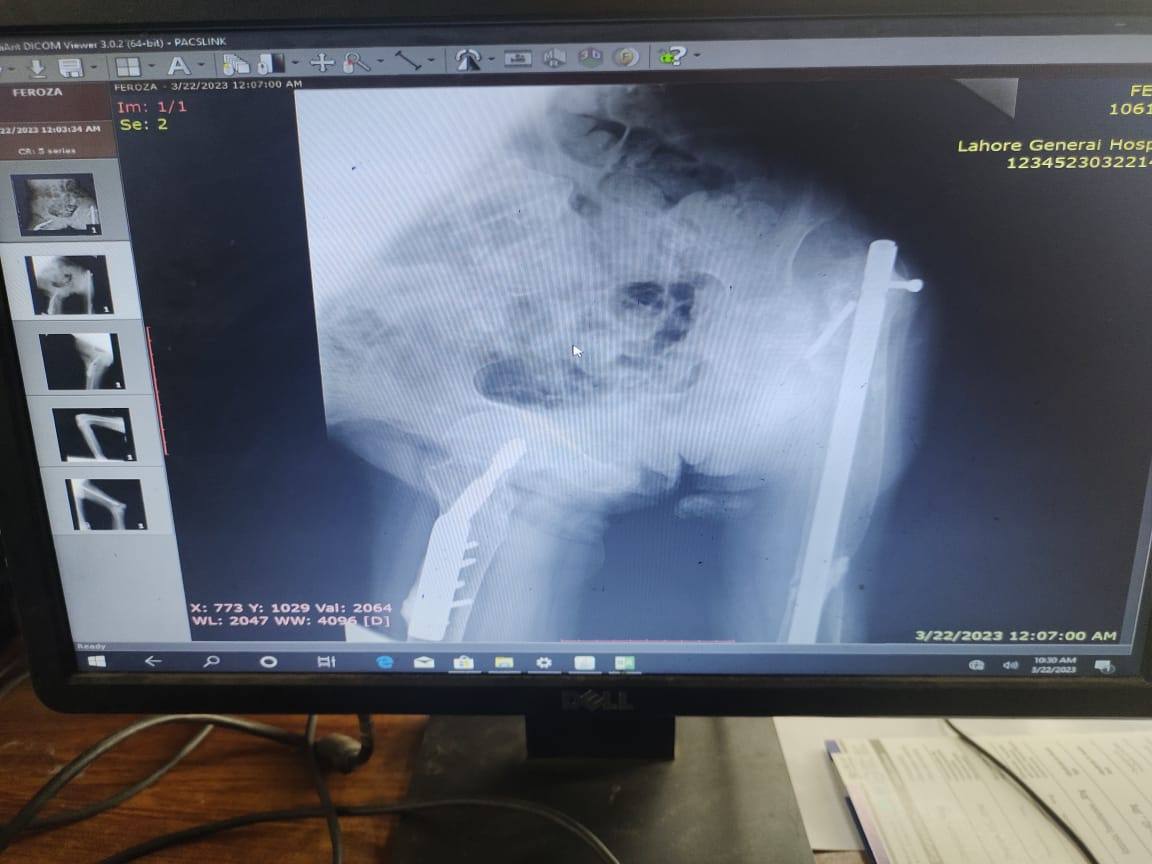

बर्साइटिस का निदान: बर्साइटिस का निदान करने के लिए, आपका आर्थोपेडिक डॉक्टर एक शारीरिक परीक्षा करेगा और आपसे आपके लक्षणों और चिकित्सा के इतिहास के बारे में पूछेगा। वे अन्य स्थितियों से इंकार करने और सूजन की सीमा का आकलन करने के लिए एक्स-रे, एमआरआई, या अल्ट्रासाउंड जैसे इमेजिंग परीक्षणों का भी आदेश दे सकते हैं। आपका डॉक्टर एक संयुक्त आकांक्षा भी कर सकता है, जिसमें सूजन वाले बर्सा से थोड़ी मात्रा में तरल पदार्थ निकाला जाता है और संक्रमण या अन्य अंतर्निहित चिकित्सा स्थितियों के लिए परीक्षण किया जाता है।